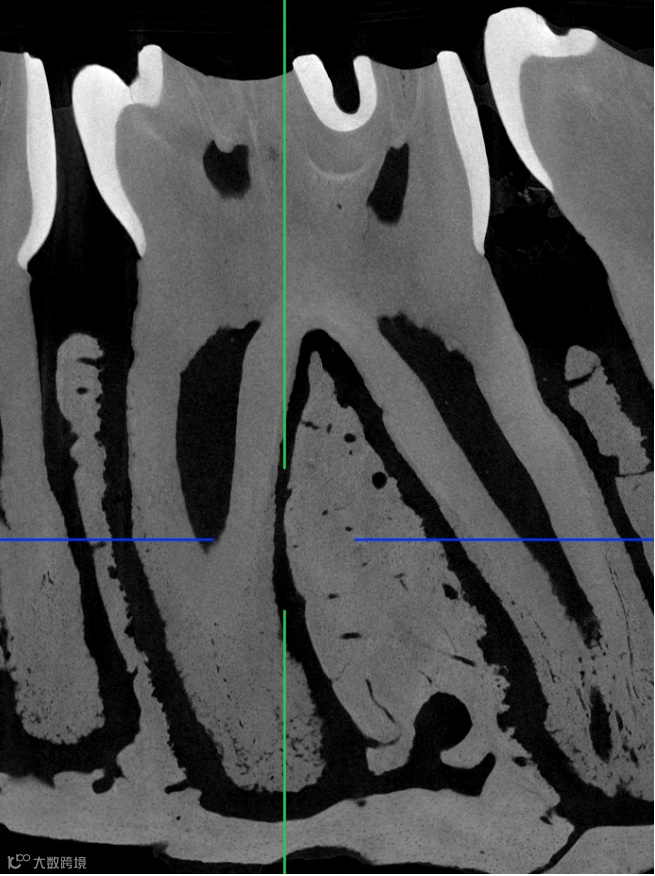

使用 Neoscan 台式显微CT

扫描小鼠下颌骨